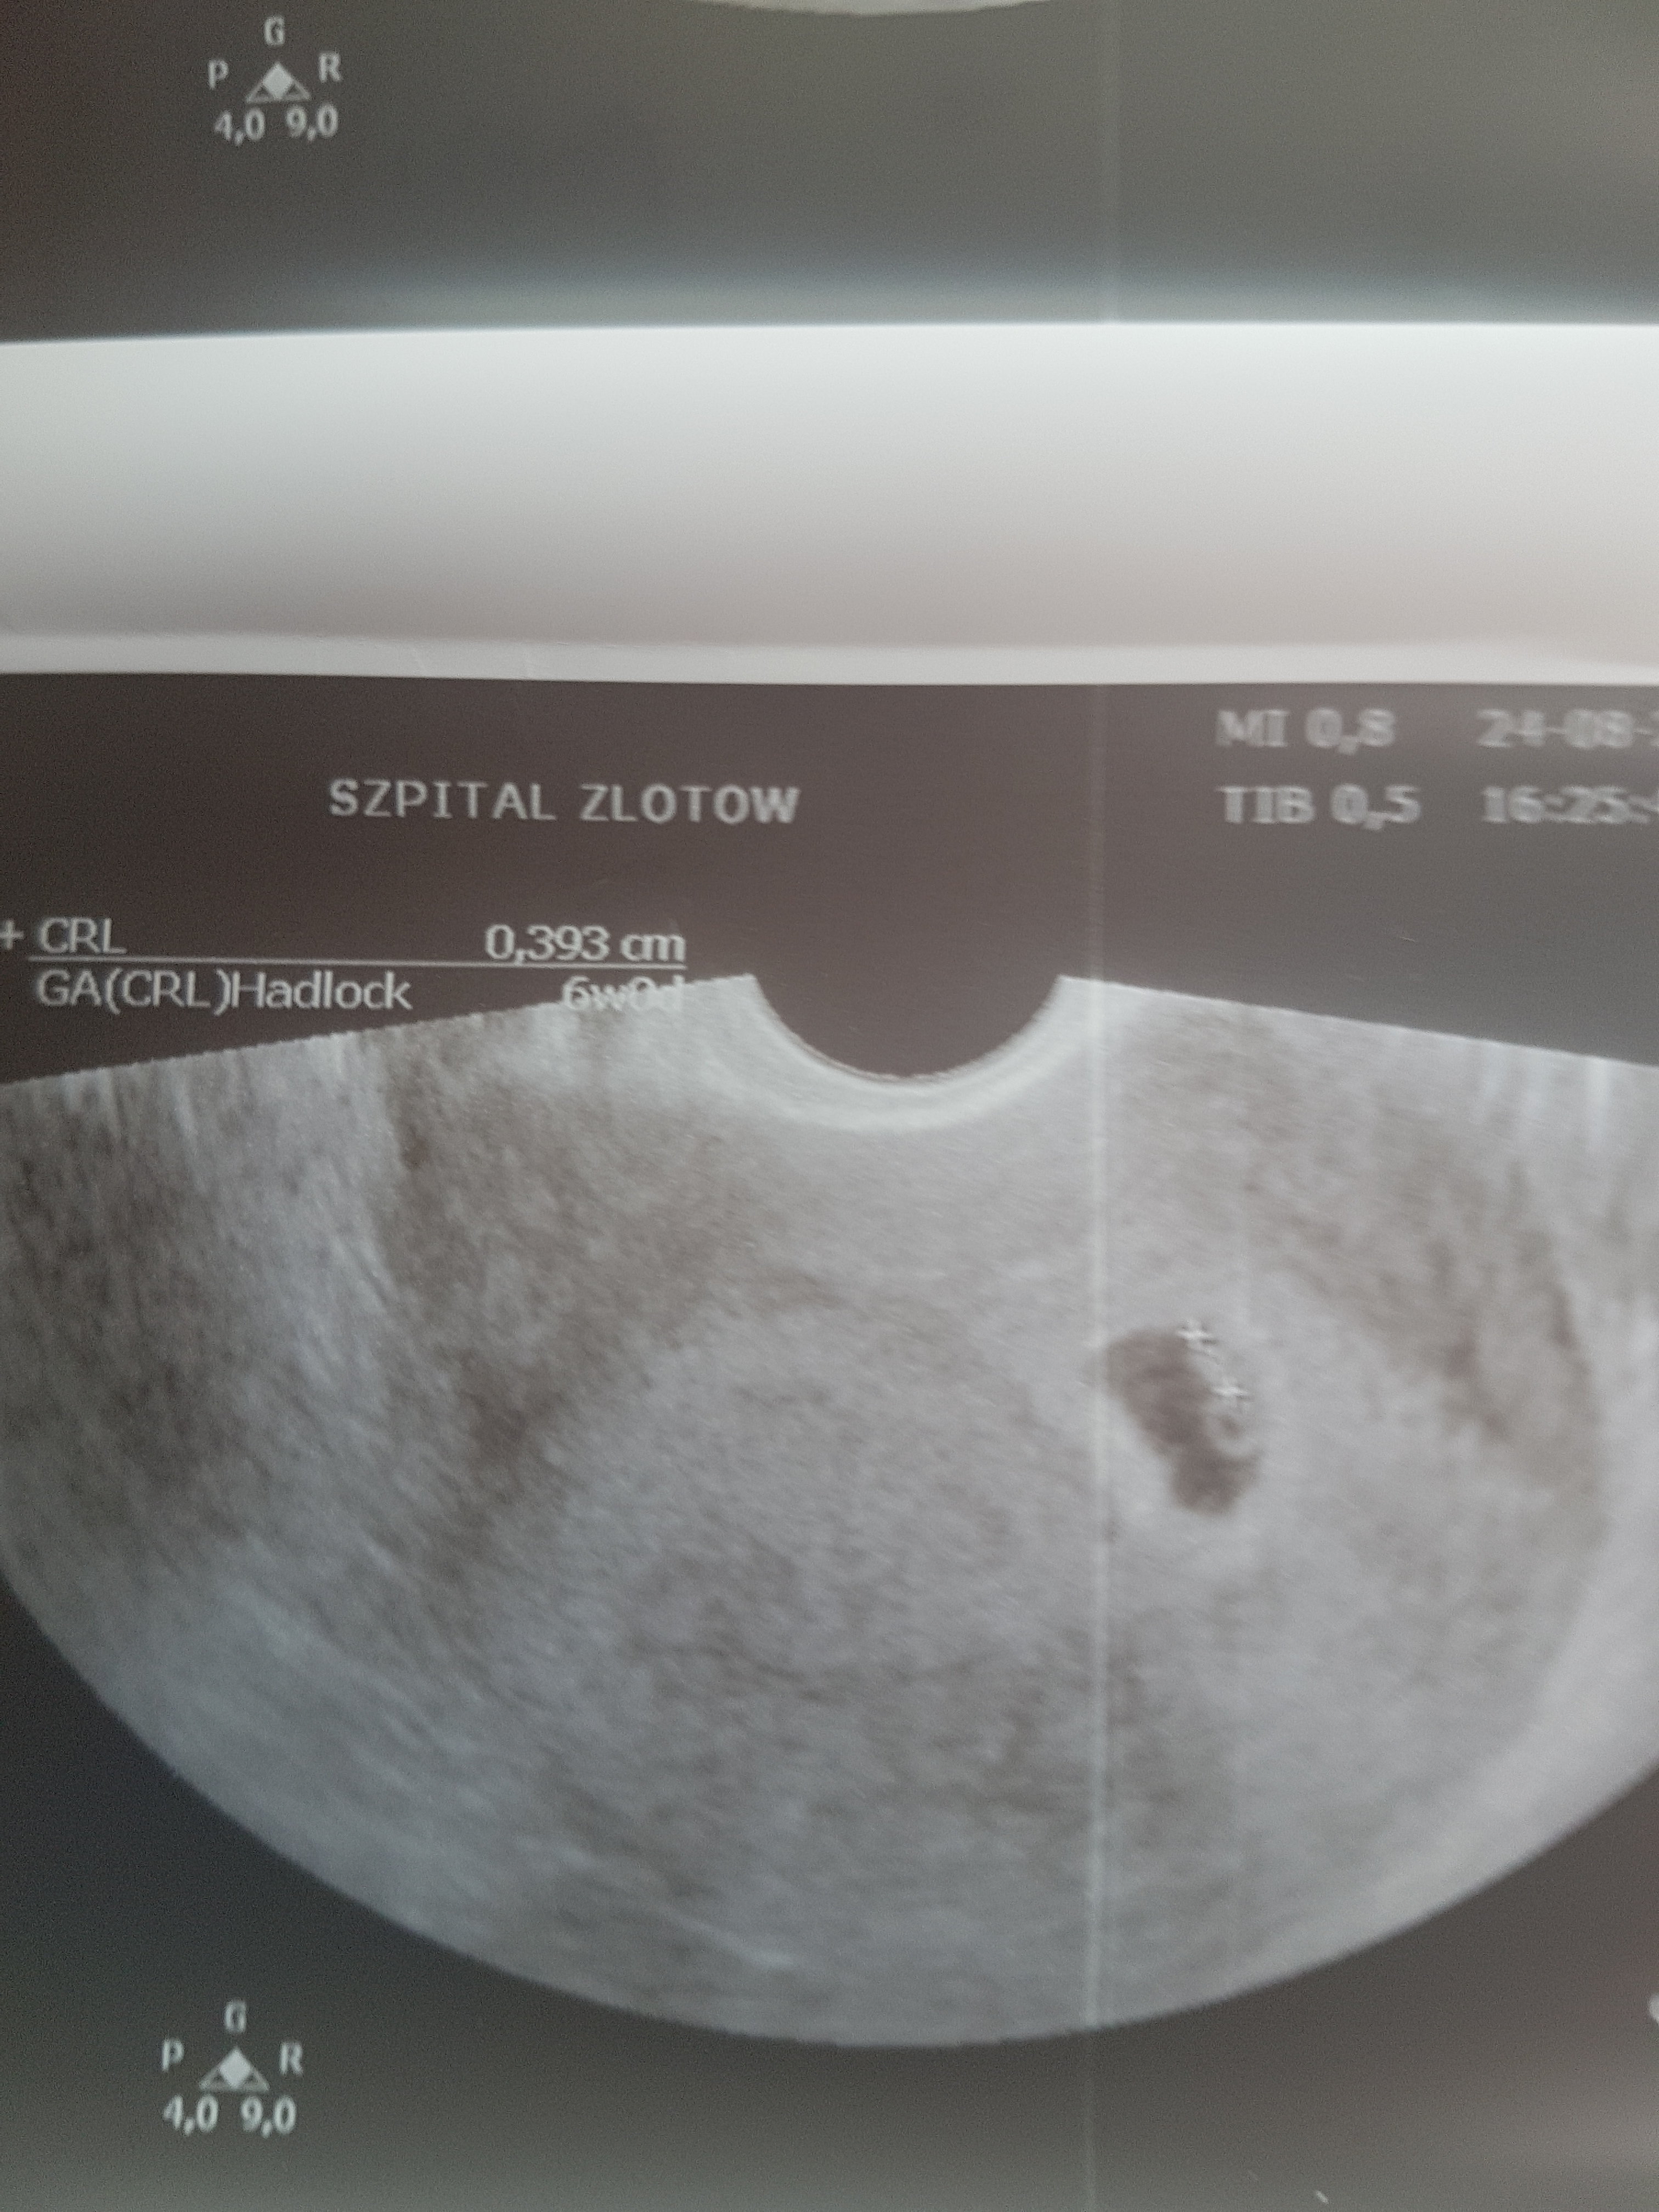

Ja już po <3 Więc tak.... Wszystko gra. Dziecko według ostatniej miesiączki to 6+1,wedlug rozmiaru dzidziusia (7,4mm)to 6+4. Termin porodu na 18 kwietnia. Biło już serce

Ok 140 uderzeń czyli tak jak powinno(oczywiscie bez słuchania, tylko oglądanie). Poszlam juz z wynikami moczu i morfologii. Krew ok. Byl zadowolony ze dużo badań już zrobiłam. Teraz mam mniej do robienia. Ale mocz zakażenie (ja zawsze coś nie tak z tym moczem mam wychodzi na badaniach) i dal antybiotyk jakiś do picia oczywiście specjalny w ciąży bezpieczny.

Mam już kartę ciązy i pierwsze zdjęcie